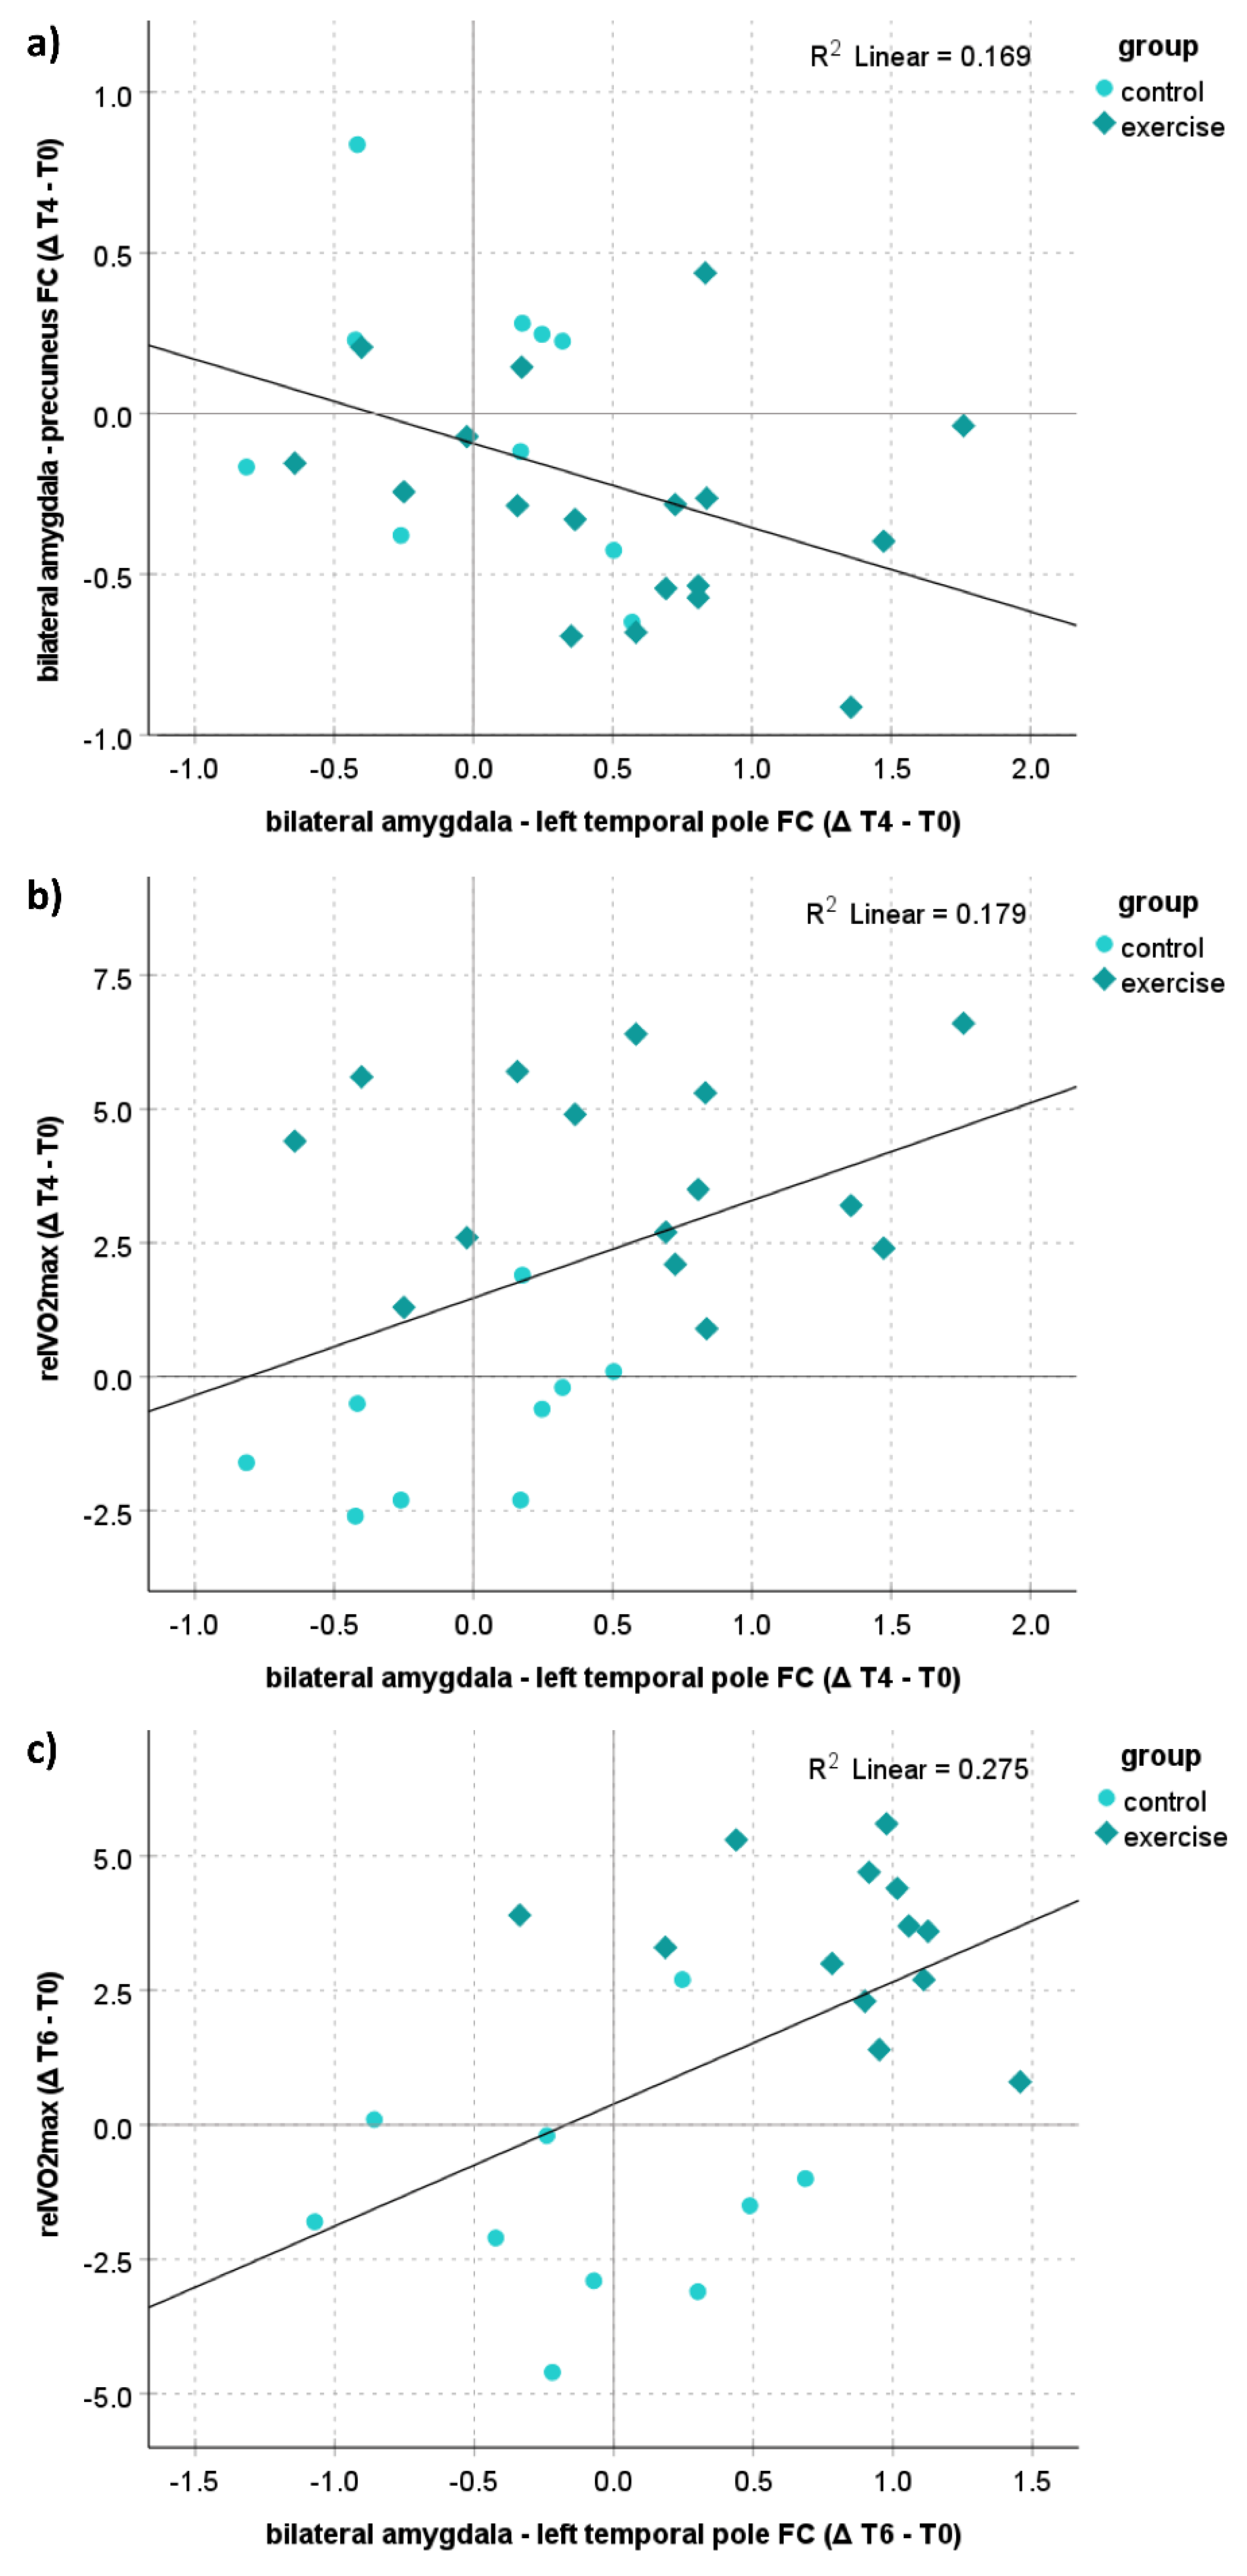

3.6. Correlation Analyses